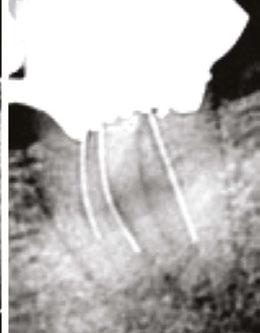

A 41-year-old male presented with a chief complaint of pain and swelling adjacent to tooth No. 10. The patient reported a history of trauma as a teenager, though he had not experienced issues until the recent onset of pain and swelling. Clinical examination revealed tenderness on the buccal gingiva around tooth No. 10, with sensitivity to percussion and biting. A small, fluctuant intraoral swelling was noted near the apex of tooth No. 10, and the tooth did not respond to vitality testing. Radiographic examination showed a large perforating internal resorptive defect near the apical third of the root (Figure 3A). CBCT (Veraviewepocs 3D R100; J. Morita) revealed significant alveolar bone loss adjacent to the defect, extending along the entire mesial side of

the apical half of the root of tooth No.10 and reaching the root of tooth No. 9 (Figures 3B and 3C).

A diagnosis of pulpal necrosis with acute apical abscess was made. All treatment options, including extraction with replacement by an implant or bridge, were discussed. The patient, motivated to retain the tooth, opted for root canal therapy and repair of the resorptive defect. Informed consent was obtained.

First visit

The patient was anesthetized with 1.7 mL of 4% articaine with 1:100,000 epinephrine (Septocaine®; Septodont®, Lancaster, Pennsylvania) via labial infiltration. Rubber dam isolation was achieved, and the tooth was accessed using a No. 2 surgical length carbide round bur. Necrotic pulp was encountered. Working length was established with a Root ZX® apex locator (Morita, Tokyo, Japan), and the canal was instrumented to a size 35 .04 Vortex Blue® rotary file (Dentsply Tulsa Dental, Johnson City, Tennessee). Care was taken to ensure that the files passed through the resorptive defect and entered the apical portion of the canal. The canal was irrigated with 5.25% sodium hypochlorite, and the EndoActivator® (Dentsply, Tulsa, Oklahoma) was used to sonically agitate the irrigant to promote thorough disinfection of the resorptive defect. The canal was dried with paper points, and calcium hydroxide (Ultracal™ XS, Ultradent Products Inc, South Jordan, Utah) was syringed into the canal and the defect. The tooth was then temporarily restored with Cavit® (3M ESPE, Neuss, Germany).

Second visit

Two weeks later, the patient returned for completion of the endodontic treatment, reporting that all symptoms had subsided. Clinical examination confirmed that the swelling had resolved. Calcium hydroxide was removed from the canal through instrumentation, irrigation, and activation with the EndoActivator. The canal was dried with paper points, and excess irrigant was removed using surgical suction with a micro-tip. A master gutta-percha cone was placed to the working length and confirmed with radiographic examination (Figure 3D). The canal was coated with EndoSequence® BC (bioceramic) sealer (Brasseler USA, Savannah, Georgia) to ensure sufficient sealer filled the resorptive defect. It was then obturated with gutta percha and BC sealer using the technique of warm vertical condensation (Figure 3E). The lingual access opening was restored with TPH Spectra® ST composite (Dentsply Sirona, Charlotte, North Carolina), and the patient was scheduled for recall to monitor healing.

At 1-year, 2-year, and 5-year recall visits, the patient was asymptomatic, and radiographs showed complete healing with full restoration of bone and lamina dura adjacent to the resorptive defect (Figures 3F and 3H). The patient expressed satisfaction with the outcome, having retained a tooth originally planned for extraction.

Figures 3A-3H: 3A. Preoperative periapical radiograph of tooth No.10 showing internal root resorption in apical third of root. There is significant alveolar bone loss adjacent to defect. 3B. Sagittal CBCT image of tooth No. 10 showing internal resorptive defect perforating on mesial aspect of root. Note adjacent alveolar bone loss extending proximally to tooth No. 9. 3C. Axial CBCT image of internal resorptive defect perforating on mesial aspect of root. There is thin layer of circumferential dentin remaining and extensive alveolar bone loss adjacent to the defect. 3D. Periapical radiograph showing gutta-percha cone fit. Gutta-percha cone passes through resorptive defect to contact apical portion of root canal. 2E. Immediate postoperative periapical radiograph of tooth No.10 once root canal was completed and resorptive defect was restored. 2F. Two-year follow-up showing complete healing of radiolucency adjacent to defect and reestablishment of PDL. 2G. Two-year follow-up CBCT. Coronal slice showing complete healing of radiolucency adjacent to defect and reestablishment of PDL. 2H. Five-year follow-up radiograph. Patient is completely asymptomatic